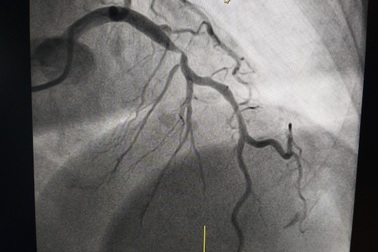

Cẩn trọng cơn đau ngực cấp tính báo động bệnh mạch vành nguy hiểmBệnh nhân 69 tuổi (Thường Tín, Hà Nội) đang ngồi bỗng dưng lên cơn đau ngực dữ dội. Khi gia đình đưa đến viện, bệnh nhân được chụp động mạch vành, phát hiện tổn thương xơ vữa gây tắc mạch, đã phải đặt stent để "thông" dòng chảy thông thoáng cho mạch vành.